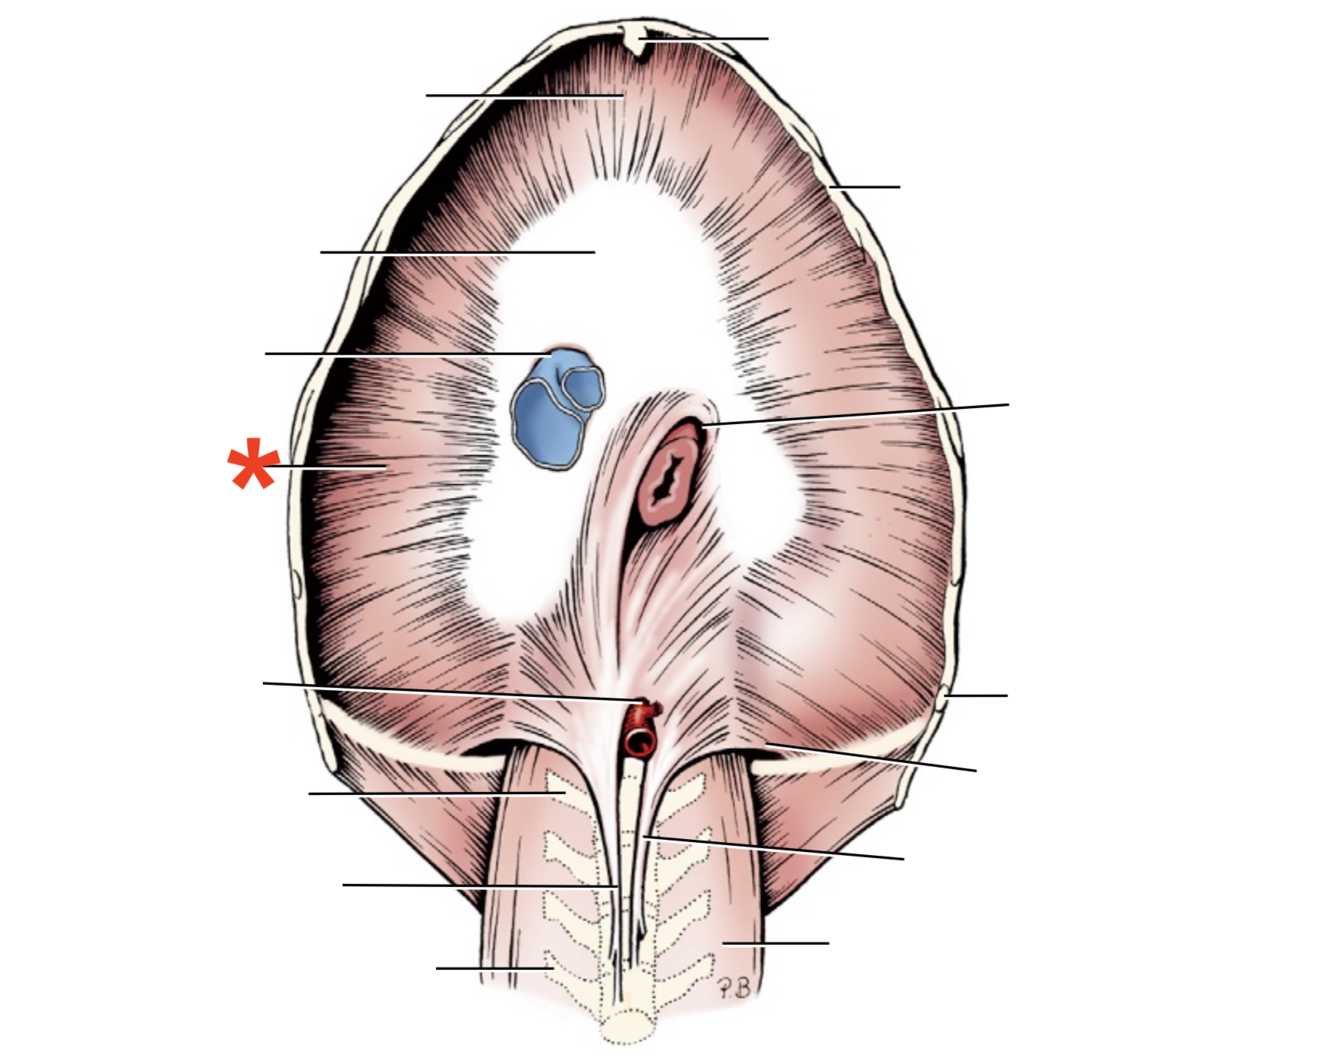

1

Q

Name given to the most cranial part of the diaphragm.

A

Cupula Diaphragmatis

2

Q

A

Pars sternalis

3

Q

A

Foramen vena cavae

4

Q

A

Pars costalis

5

Q

A

Hiatus aorticus

6

Q

A

Arcus lumbocostalis

7

Q

A

Hiatus oesophagus

8

Q

A

Crus sinistrum

9

Q

A

Crus dextrum

10

Q

A

Centrum tendineum

11

Q

A

Corona muscularis